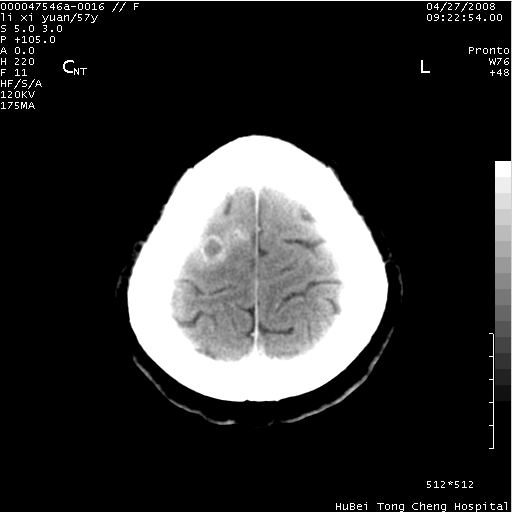

以下是引用余辉在2008-4-27 14:02:00的发言:[br]病灶位于中央沟前方?位于额叶?高密度灶,灶周水肿不明显,病灶似沿脑沟走行,强化明显,局部层面呈现环状强化,考虑1脑表面血管性疾病,如血管瘤,血管扩张,灶内血栓形成,其次考虑肿瘤如脑膜瘤、转移瘤,胶母等

以下是引用形影不离在2008-4-27 14:13:00的发言:[br]考虑胶质瘤可能性大,不排除慢性炎性肉芽肿。建议mri检查。